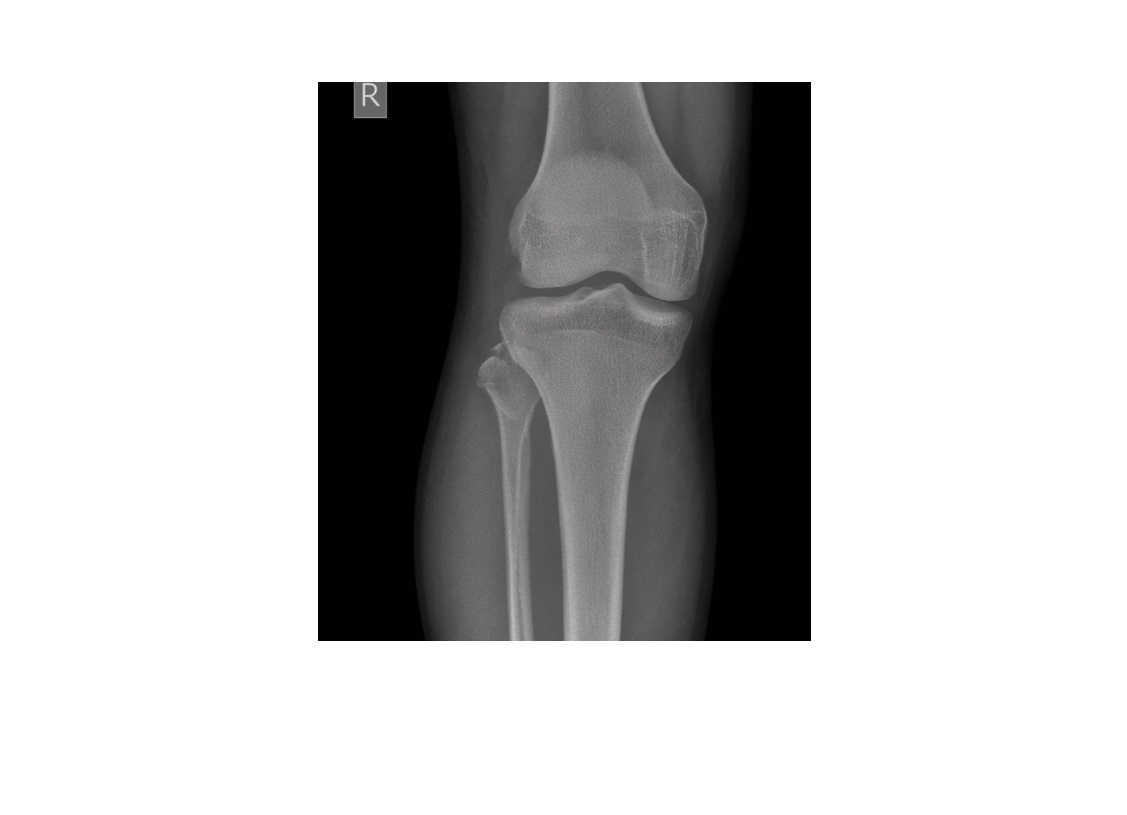

Segond fracture

Lateral tibial plateau

Associated with ACL tear (75%) and internal rotation

MR SL = Medial Reverse Lateral Segond

Reverse Segond fracture

Medial tibial plateau

Associated with PCL tear with external rotation. Associated with medial meniscus injury.